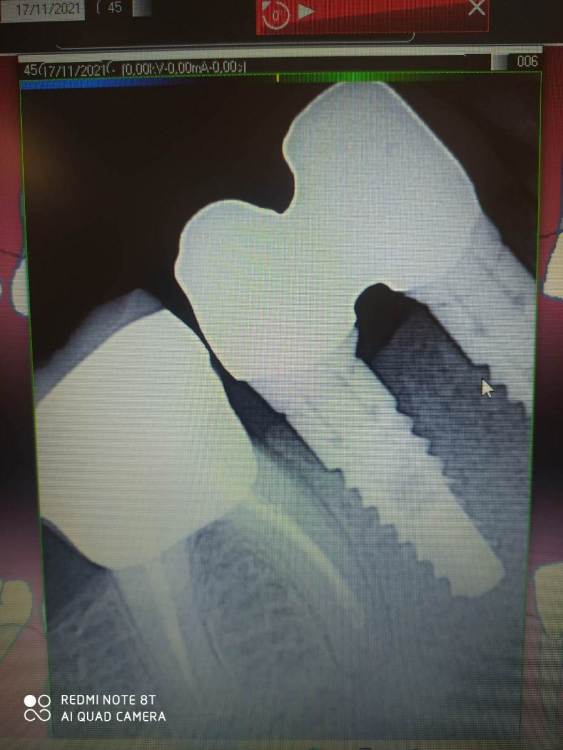

Evgen-Vozhd Опубликовано 17 ноября, 2021 Поделиться Опубликовано 17 ноября, 2021 Добрый день,коллеги. Пришла пациентка из другой клиники, не устроило качество коронок (был запах). Сделали новые абатменты и каркасы- они на фото. Прилегание абатментов к платформе на мой взгляд неплотное. Вопрос: это брак или у биогоризонта так и должно быть? Ссылка на комментарий

Evgen-Vozhd Опубликовано 17 ноября, 2021 Автор Поделиться Опубликовано 17 ноября, 2021 Раньше на Биогоризонте не работал, поэтому и сомневаюсь в прилегании абатментов Ссылка на комментарий

bakagaidzin Опубликовано 17 ноября, 2021 Поделиться Опубликовано 17 ноября, 2021 у вас снимок под углом сделан.Вы в оптике прилегание перед фиксацией не проверяли? Ссылка на комментарий

Evgen-Vozhd Опубликовано 17 ноября, 2021 Автор Поделиться Опубликовано 17 ноября, 2021 Не понял про оптику. Как под десной ей проверить. К аналогам прилегает плотно. Слепки снимал трансферами от Миса. Коллеги сказали, что они подходят. Аналоги тоже Мис. Сканбоди брали от Биогоризонта, премилы тоже Ссылка на комментарий

Evgen-Vozhd Опубликовано 24 ноября, 2021 Автор Поделиться Опубликовано 24 ноября, 2021 21.11.2021 в 18:44, dentikl сказал: Сделал снимок с оригинальной платформой Биогоризонт. Точности прилегания по платформе всё равно не вижу. Хз... ощущение, что щель между юбкой абатмента и платформой. Ссылка на комментарий

АнтонТЛТ Опубликовано 24 ноября, 2021 Поделиться Опубликовано 24 ноября, 2021 (изменено) 4 минуты назад, АнтонТЛТ сказал: Проекция снимка не правильная, но мезиальный выглядит докрученным. Дистальный не докручен. Ключём затягивали? Изменено 24 ноября, 2021 пользователем АнтонТЛТ Ссылка на комментарий

Evgen-Vozhd Опубликовано 24 ноября, 2021 Автор Поделиться Опубликовано 24 ноября, 2021 6 часов назад, АнтонТЛТ сказал: Ключём затягивали? Затянул 20н/см. Абатменты по ощущениям садятся как надо, без сопротивления при закручивании винта. только по снимку непонятки Ссылка на комментарий